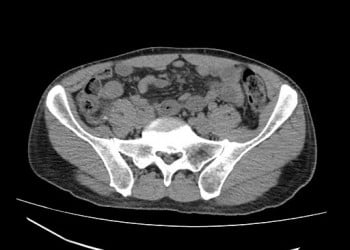

- BT’nin normal olması KİBAS’ı (kafa içi basınç artışını) tamamen ekarte etmez veya menenjitin dışlandığını göstermez. BT, kitle etkisini (abse, tümör, kanama) veya immünsüpresyon, SVO öyküsü, fizik muayenede fokal defisit, papilödem, yeni tanı epilepsi gibi durumlarda olası kafa içi patolojileri dışlamak için LP öncesi bir güvenlik basamağıdır. Ama tabii ki menenjitin kendisi BT’de görülmeyebilir.